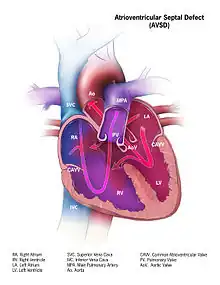

Atrioventricular septal defect (AVSD) or atrioventricular canal defect (AVCD), also known as "common atrioventricular canal" or "endocardial cushion defect" (ECD), is characterized by a deficiency of the atrioventricular septum of the heart that creates connections between all four of its chambers. It is a very specific combination of 3 defects:

1) Atrial Septal Defect (ASD), a hole in the wall between the right and left atria;

2) Ventricular Septal Defect (VSD), a hole in the wall between the right and left ventricles; and

3) Abnormalities of the mitral and/or tricuspid valves.[1][2]

Defective embryonic formation of the heart results in multiple holes between the heart chambers. In AVSD, all four chambers are connected, but the exact characteristics of holes and malformations may vary between patients. Even within the categories of "complete" and "partial" AVSD, multiple morphologies exist, with varying clinical consequences. Clinical and physiological manifestations of disease may also change over time, in response to continued stress.[3]

- In the complete AVSD (CAVSD), there is a large ventricular component beneath either or both the superior or inferior bridging leaflets of the AV valve. The defect involves the whole area of the junction of the upper and lower chambers of the heart, i.e. where the atria join the ventricles. There is a large hole between the lower portion of the atria and the upper or 'inlet' portion of the ventricles and this is associated with a significant abnormality of the valves separating the atria from the ventricles. The valves in effect become a common atrio-ventricular valve, and the severity of the defect depends largely on the supporting attachments of the valve to the ventricles and whether the valve allows dominant flow from the right atrium to right ventricle and from left atrium to left ventricle ("unbalanced" flow). The overall problems are similar to those of VSD but are more complicated. There is an increased flow of blood to the lungs through both the ventricular and atrial components of the defect. In addition, the abnormal atrio-ventricular valve invariably leaks, so that when the ventricles contract, blood flows not only forwards to the body and the lungs, but also backwards into the atria. The back-pressure effect on the atria causes congestion of blood in the left atrium in particular, and this in turn causes congestion in the veins draining the lungs. The effect on the baby is to worsen the heart failure that is associated with an isolated VSD and to hasten the onset of pulmonary hypertension. It should be mentioned that CAVSD is found in approximately one-third of babies who have Down syndrome, but it also occurs as an isolated abnormality.